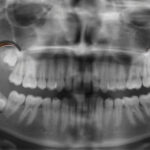

In earlier populations, wisdom teeth commonly erupted without difficulty. In modern mouths, space is often limited. This can cause these teeth to emerge sideways, remain beneath the gum line, or break through only partway. Ironically, teeth once associated with maturity now often require removal.